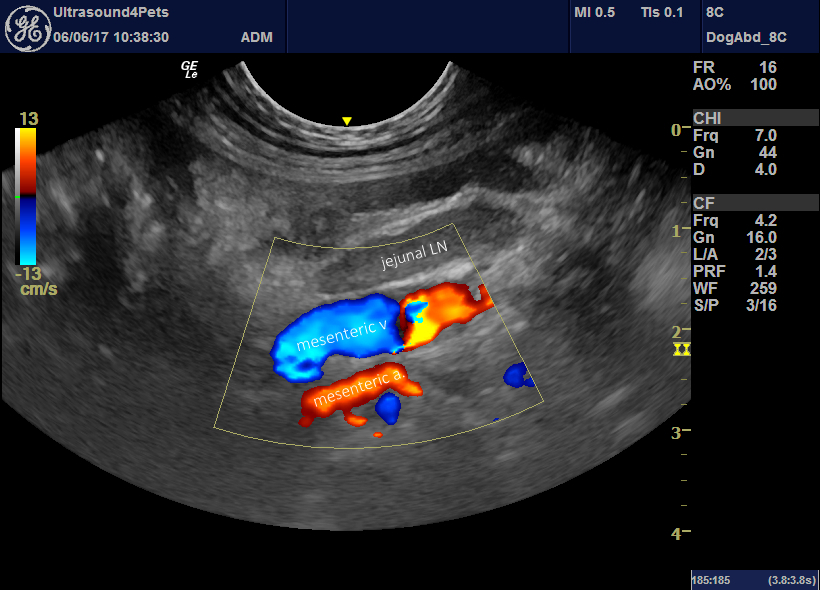

From northwestvetimage.com

Northwest Veterinary Imaging Dog Mesenteric Torsion Mesenteric torsion (mt) is a rotation of the intestines around the mesenteric axis causing luminal obstruction. Intestinal volvulus is a rare disorder in dogs in which there is rotation of a segment of the intestine on its mesenteric axis (gillespie et al.,. Mesenteric torsion is a pathological rotation of the intestinal tract around the axis of the mesenteric root, resulting. Dog Mesenteric Torsion.